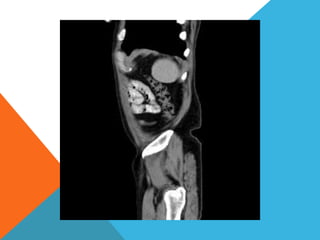

El paciente presentó síntomas de sangrado digestivo y pérdida de peso. Exámenes revelaron gastritis crónica asociada a H. pylori. Un tumor fue descubierto en una colonoscopia normal. La cirugía removió un tumor fibroide solitario, una rara neoplasia mesenquimal que usualmente crece lento y tiene bajo potencial de malignidad. El pronóstico después de la remoción quirúrgica es generalmente bueno.